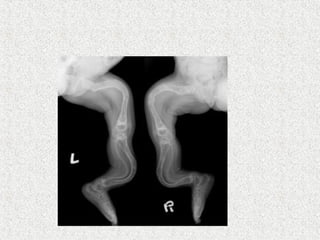

ļ‚ž Anterolateral bow or proximal varus

deformity of the femur

ļ‚ž Anterior or anteromedial bow of the tibia

ļ‚¢ By 6 yrs severe deformity of long bones & spine